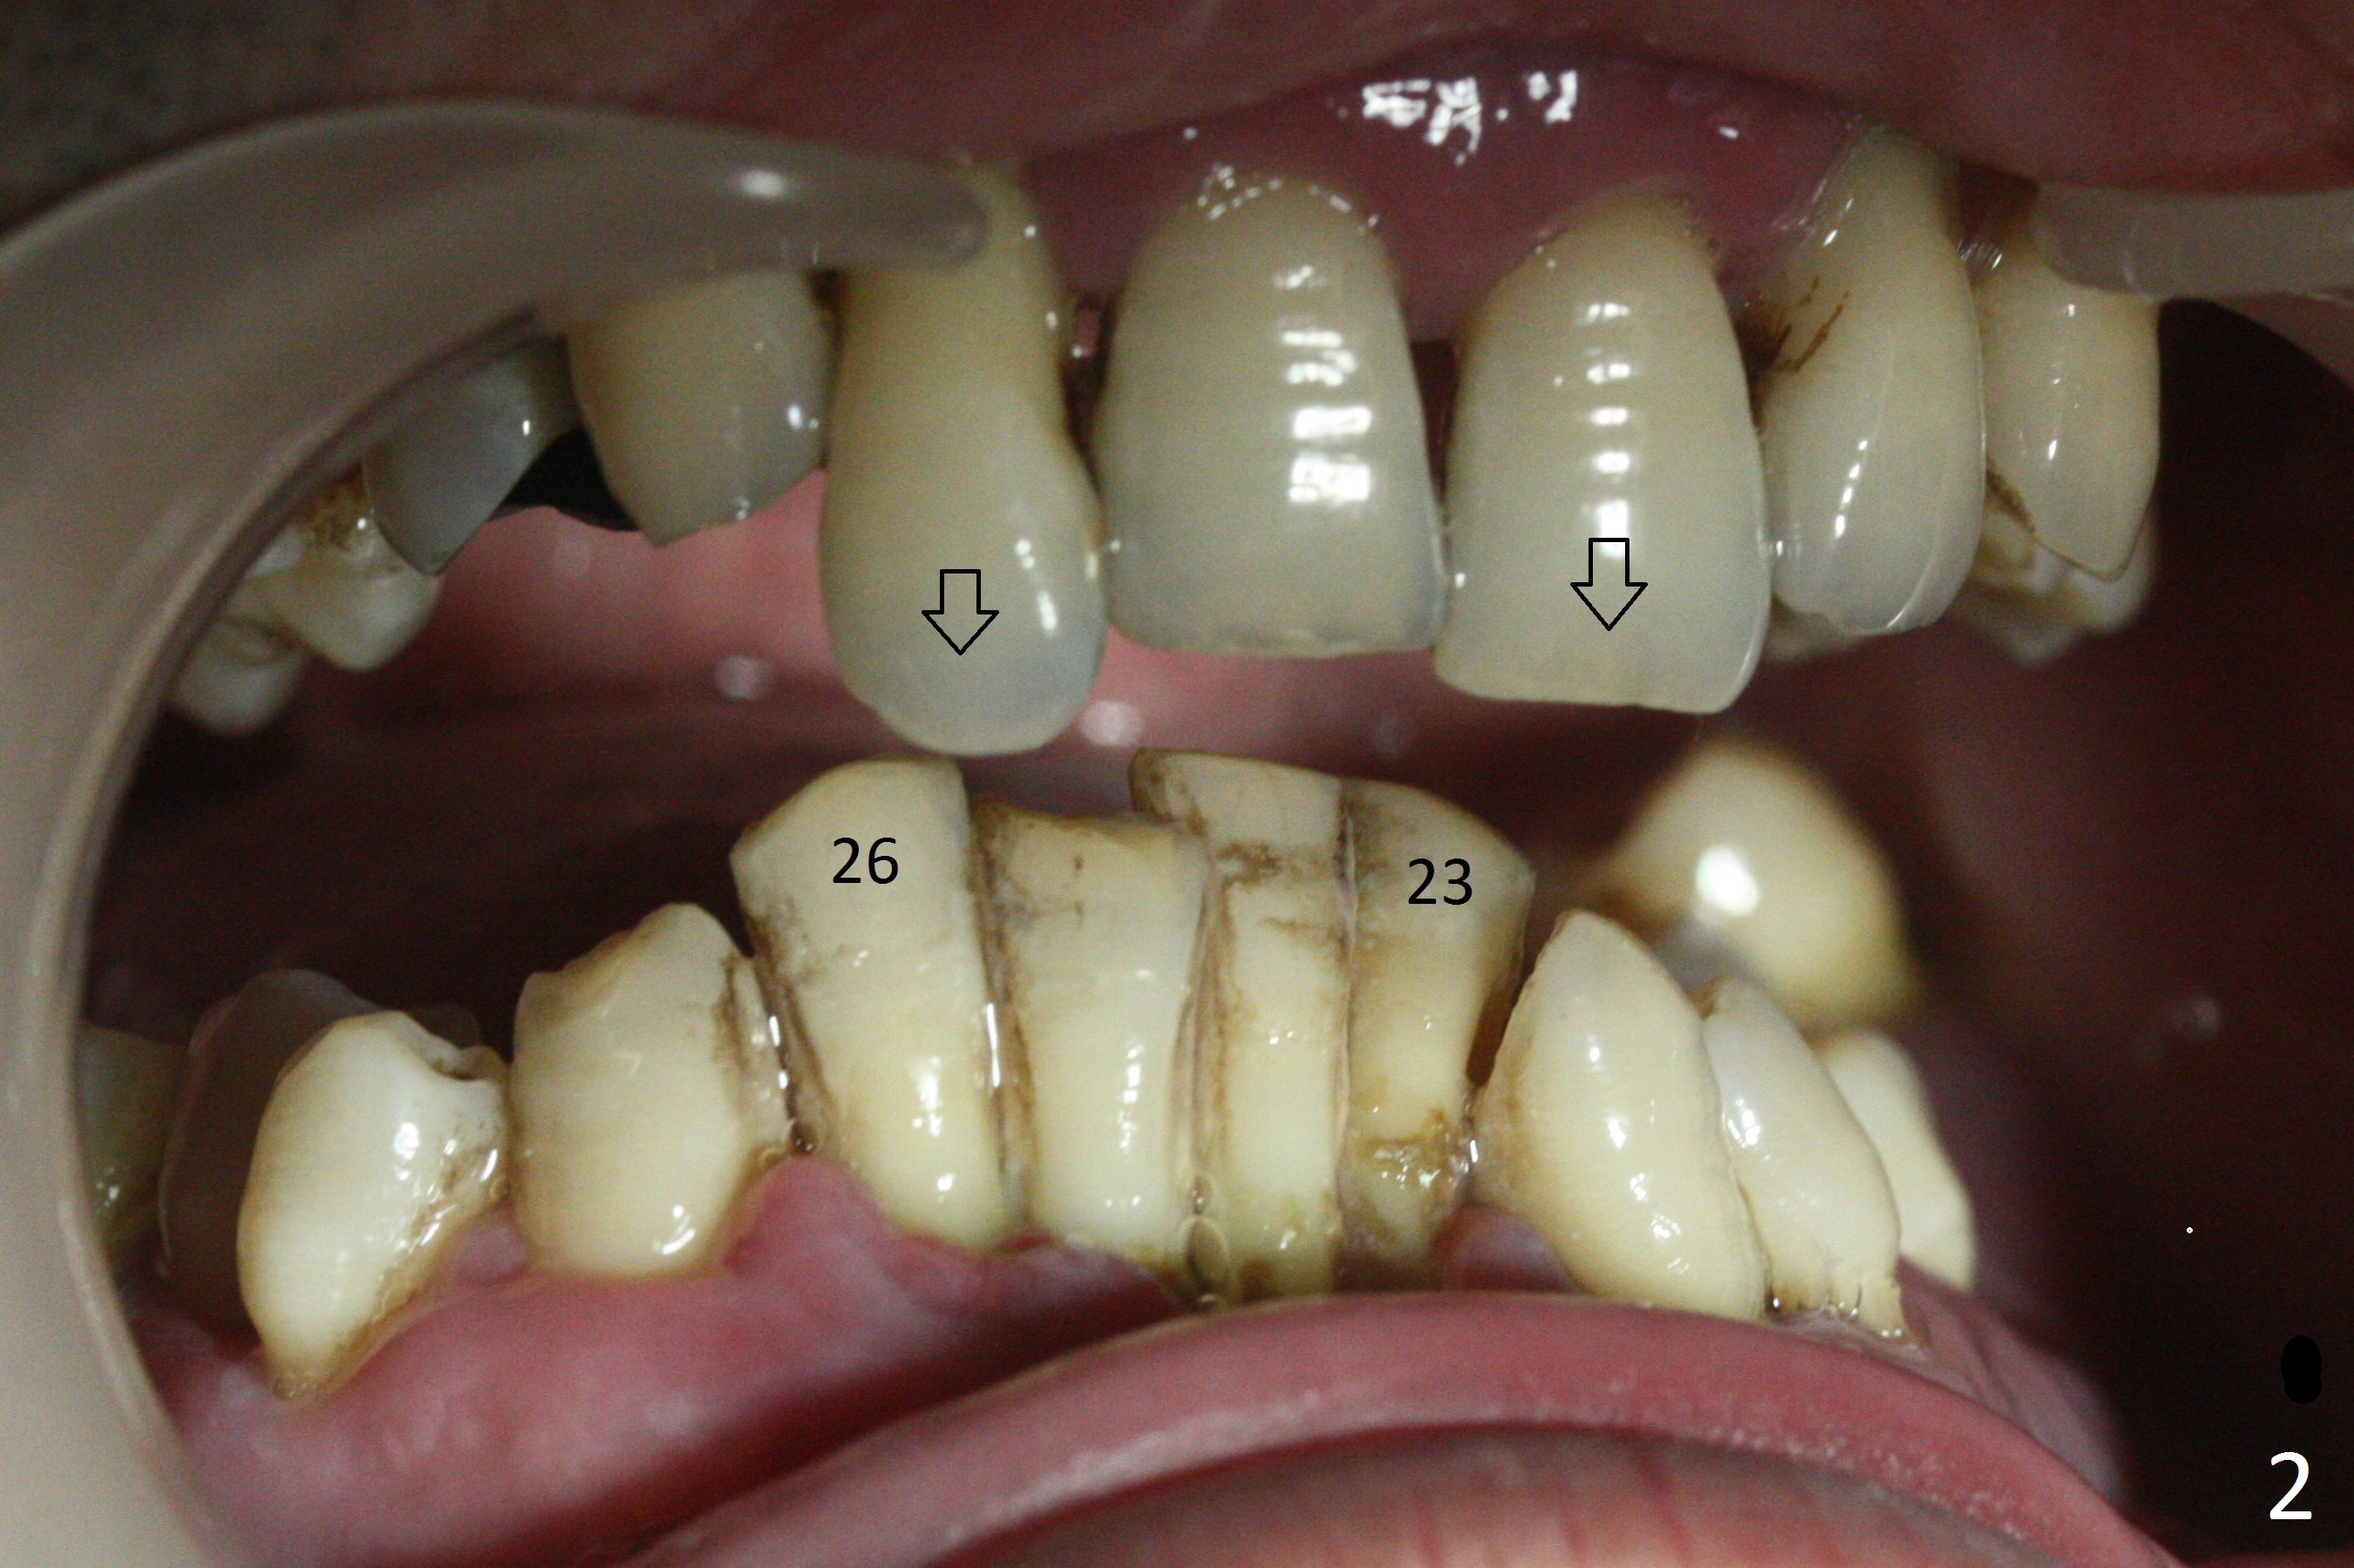

A 36-year-old man (ex-smoker) has advanced chronic periodontitis (Fig.1-5). His chief complaint is "I cannot chew on the right side now because of pain (Fig.1: #3 abscess <) and the bottom front teeth are loose (Fig.2,5: #23-26)". He has not masticated on the left side because of the mobile teeth. Due to finance, implants will be placed at #3,4 (Fig.12), 23 and 26 at the appointments of scaling & root planing.

Class II Division II malocclusion (Fig.2,6) will make it difficult to restore #23-26 implant-supported FPD. Although the teeth #7-10 may need to be replaced later (Fig.7,8), enameloplasty will be conducted for #7-10 (Fig.9 white area; Fig.12 black circles (gross reduction)) prior to #23-26 extraction and implant placement (Fig.10). To be flexible in restoration (angulation) and possible future hybrid denture, 2-piece narrow implants will be placed (3.0 or 3.3 mm) instead of 1-piece ones. In fact CBCT shows that the narrowest regular implant (3.8 mm) can be placed in the lower anterior region (Fig.13-15).